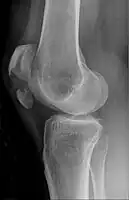

![]() | |

| A fracture of the patella seen on a lateral view | |